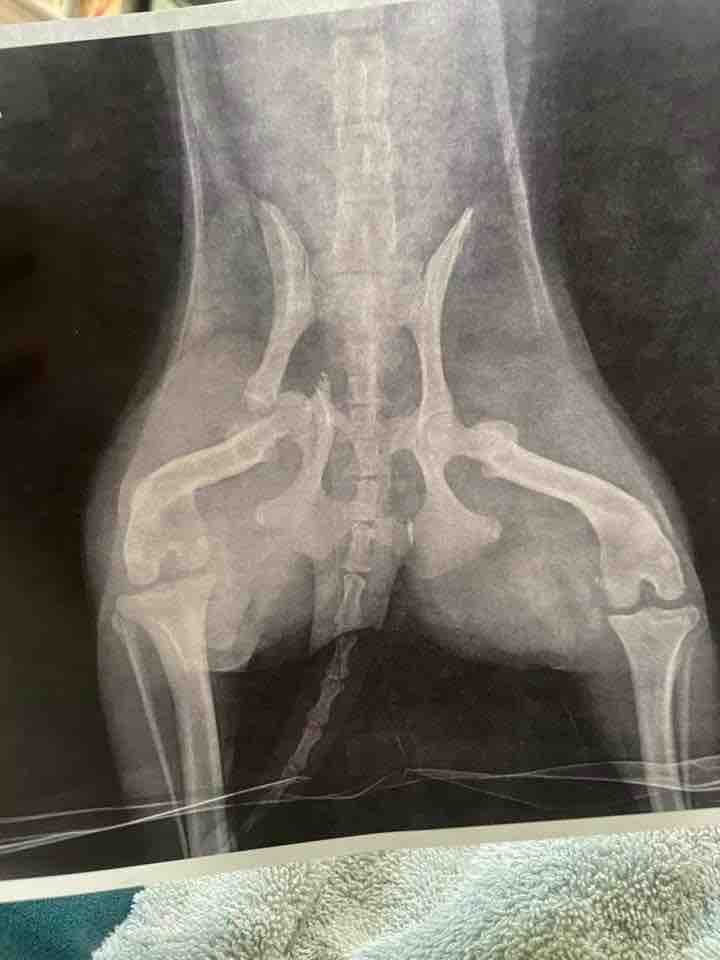

With that being said, our precious pup is in stable condition but definitely banged up. He just got some really good pain killers, got a bunch of x-rays, and had a broken tooth removed that he suffered from while rolling underneath the man’s car. He’s going to need surgery on his right pelvis to get him using his hind legs again. He has a very substantial fracture that is rendering him immobile.

He will require surgery to put his pelvis back together. His surgeon estimates the cost being $12,000. But she will not know until she gets him on the table and assesses any potential further damage. Of course we must pay out of pocket for this because the man responsible for hurting him so badly didn’t bother to stop the car let alone give us any insurance information to cover the cost of the medical bills.